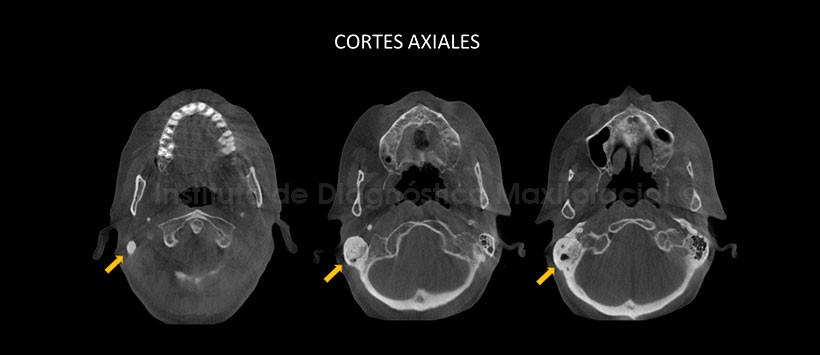

A la evaluación de la tomografía volumétrica (CBCT) en la reconstrucción panorámica de ATM (Figura2), en cortes axiales (Figura 3), coronales (Figura 4) se observa alteración en la estructura y tamaño de la apófisis mastoidea donde apreciamos zonas hiperdensas que obliteran las celdillas mastoideas. En los cortes sagitales (Figura 5) se aprecia ademas espacios discales conservados.

En las reconstrucciones 3D (Figura 6 y 7), se aprecia la comparación de ambas lados, y la alteración anatomica y morfológica de la apofisis mastoidea derecha.